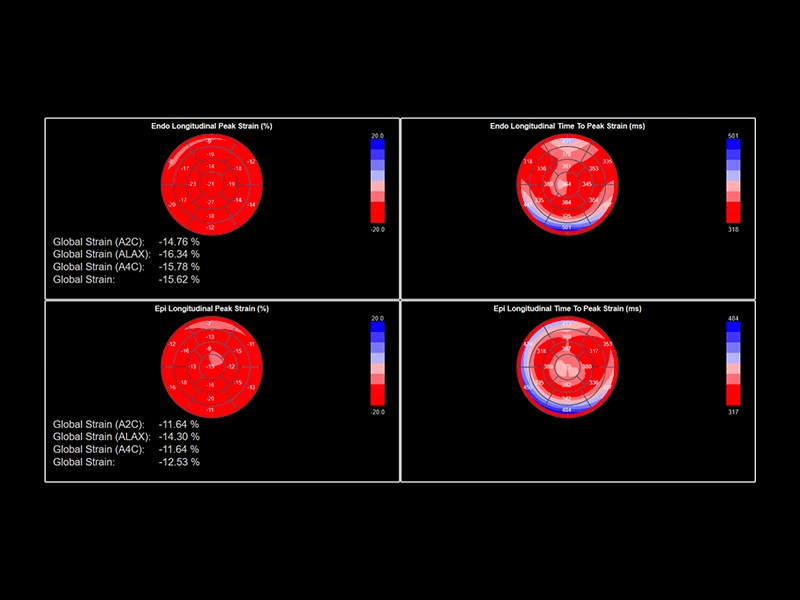

MyLab™C25 - Xstrain

MyLab™C25 - Xstrain

MyLab™E80 - XStrain LA

MyLab™E80 - XStrain LA

MyLab™E80 - XStrain LV - Bull's eye

MyLab™E80 - XStrain LV - Bull's eye

MyLab™9 Platform - XStrain4D technology for volumetric heart assessment by coronary territories

MyLab™9 Platform - XStrain4D technology for volumetric heart assessment by coronary territories

MyLab™9 Platform - XStrain™ 2D speckle tracking technologies for global and regional function

MyLab™9 Platform - XStrain™ 2D speckle tracking technologies for global and regional function

MyLab™Sigma - Left Ventricle XStrain 2D analysis

MyLab™Sigma - Left Ventricle XStrain 2D analysis

MyLab™X8 Platform - Zero-click strain evaluation with XStrain™2D

MyLab™X8 Platform - Zero-click strain evaluation with XStrain™2D

MyLab™X8 Platform - Volumetric model of the left function with XStrain4D

MyLab™X8 Platform - Volumetric model of the left function with XStrain4D

MyLab™X90 - XStrain™ LV Automatic assessment of global longitudinal strain in the left ventricle

MyLab™X90 - XStrain™ LV Automatic assessment of global longitudinal strain in the left ventricle

MyLab™X5 - XStrain

MyLab™X5 - XStrain

MyLab™X6 - XStrain

MyLab™X6 - XStrain

MyLab™X7 - XStrain

MyLab™X7 - XStrain

MyLab™X7 - XStrain4D

MyLab™X7 - XStrain4D

MyLab™A70 - XStrain RV